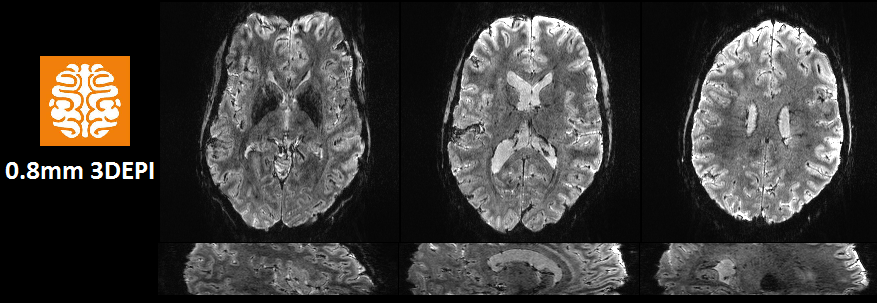

Exciting opportunity to come and join the @WCHN_UCL Maguire Memory Lab using our fab new 7T MRI scanner to study memory! More info here: tinyurl.com/y3ukmbgv First high resolution 3D-EPI on the #7T #Terra looking good! 🤟

First high resolution 3D-EPI on the #7T #Terra looking good! 🤟